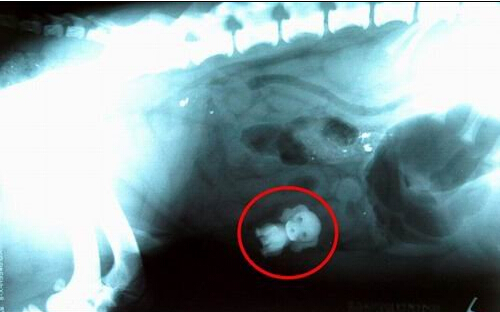

据英国媒体报道,人们也许从未听过“狗吞狗”的事情,日前,英国柴郡一只宠物狗在接受兽医体检时意外地发现它的胃中竟有一只“小狗”,只不过这是一只玩具狗而已。 经兽医X光扫描显示,一只斯班尼犬胃中有一个玩具狗 经过两个小时,兽医终于从宠物狗体内取出玩具狗 乔安尼-达顿和7岁女儿艾德琳发现他们的斯班尼犬——阿尔菲开始拒绝吃食和喝水,之后表现出严重的病态。达顿说:“阿尔菲看上去非常痛苦,这并不像平时的它,因此我们立即将它送到了医院。”

当兽医对它进行X光扫描时,发现它的胃中竟有一只玩具狗,达顿猜测很可能是这条斯班尼犬趁女儿不在时,偷偷地进入她的房间,并将这个玩具狗吞入口中。兽医马克-阿灵顿(Mark Allington)说:“我们进行X光扫描时,很显然地看到它的胃中有一只玩具狗,经过两个小时的手术,才将玩具狗取出来。” 目前恢复健康的阿尔菲又像以往那样活蹦乱跳地在院子里奔跑着。 想必大家读完这则新闻也为这只狗狗捏了一把汗吧,幸亏只是玩具,如果脱下了什么锋利的东西,那就不得了。幸好最后玩具狗顺利从狗狗体内取出,希望这只狗狗今后可一定要吸取教训,不要随便乱吃东西了。 |